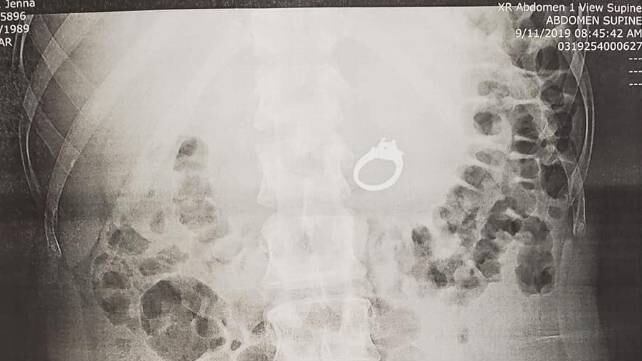

La pareja terminó en un hospital y una radiografía demostró que el anillo estaba en su estómago, por lo que los médicos decidieron realizar una endoscopia y finalmente lograron extraer el anillo.